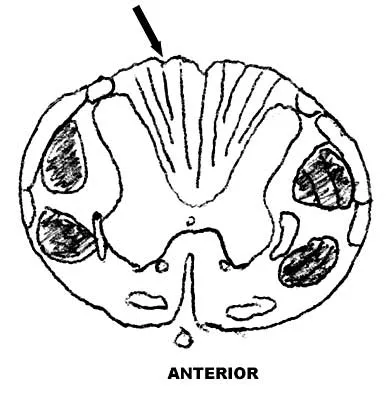

Figure 9 shows a cross-sectional view of the spinal cord at the lower cervical level. Injury to the structure indicated by the black arrow will lead to what neurologic deficit?

Correct Answer: Unilateral loss of position sense, proprioception, and vibratory sense below the level of the injury

Explanation:

The arrow is pointing to the posterior columns of the spinal cord that transmit position sense, vibratory sense, and proprioception. There are no motor tracts in the posterior columns. Bohlman H, Ducker T, Levine A: Spine trauma in adults, in Herkowitz HH (ed): The Spine, ed 4. Philadelphia, PA, WB Saunders, 1992, p 911.